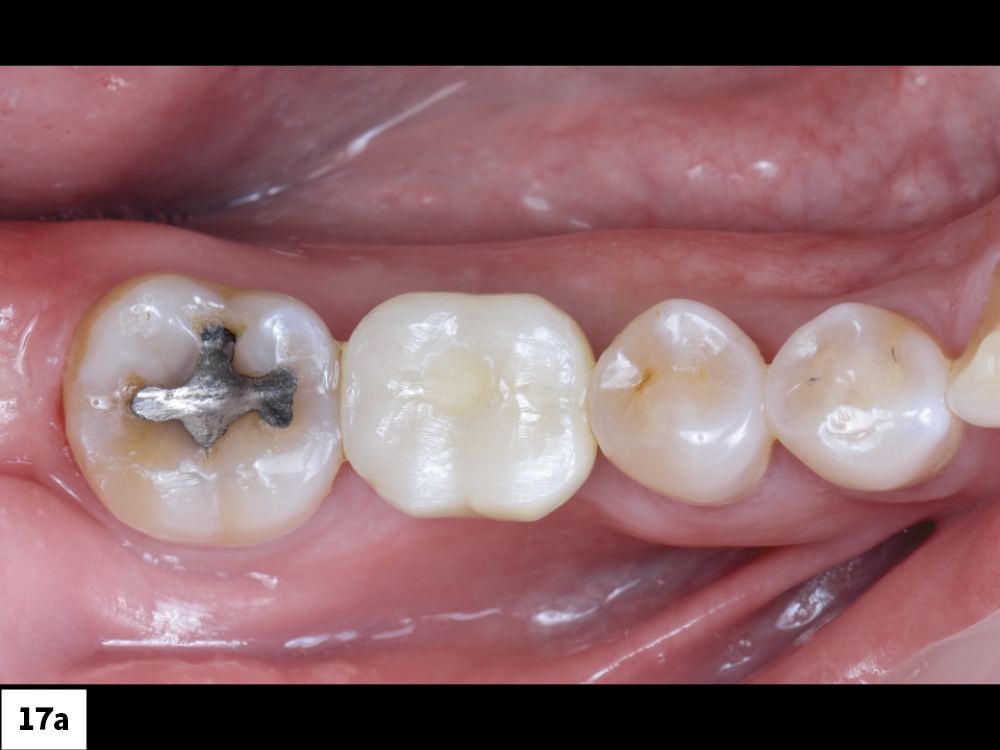

Final BruxZir Esthetic Screw-Retained Crown

Access Channel Filled with Teflon Tape

Figures 17a, 17b: The final BruxZir Esthetic screw-retained crown was fabricated by Glidewell. After it was seated, the access channel was filled with Teflon tape and sealed with composite.

Figures 18a, 18b: The final restoration seated perfectly without the need for any adjustment. The custom healing abutment created an emergence profile that allowed the final restoration to blend seamlessly with the adjacent teeth and appear to emerge from the tissue like a natural tooth. The result blends well with the adjacent dentition, restoring both function and esthetics.